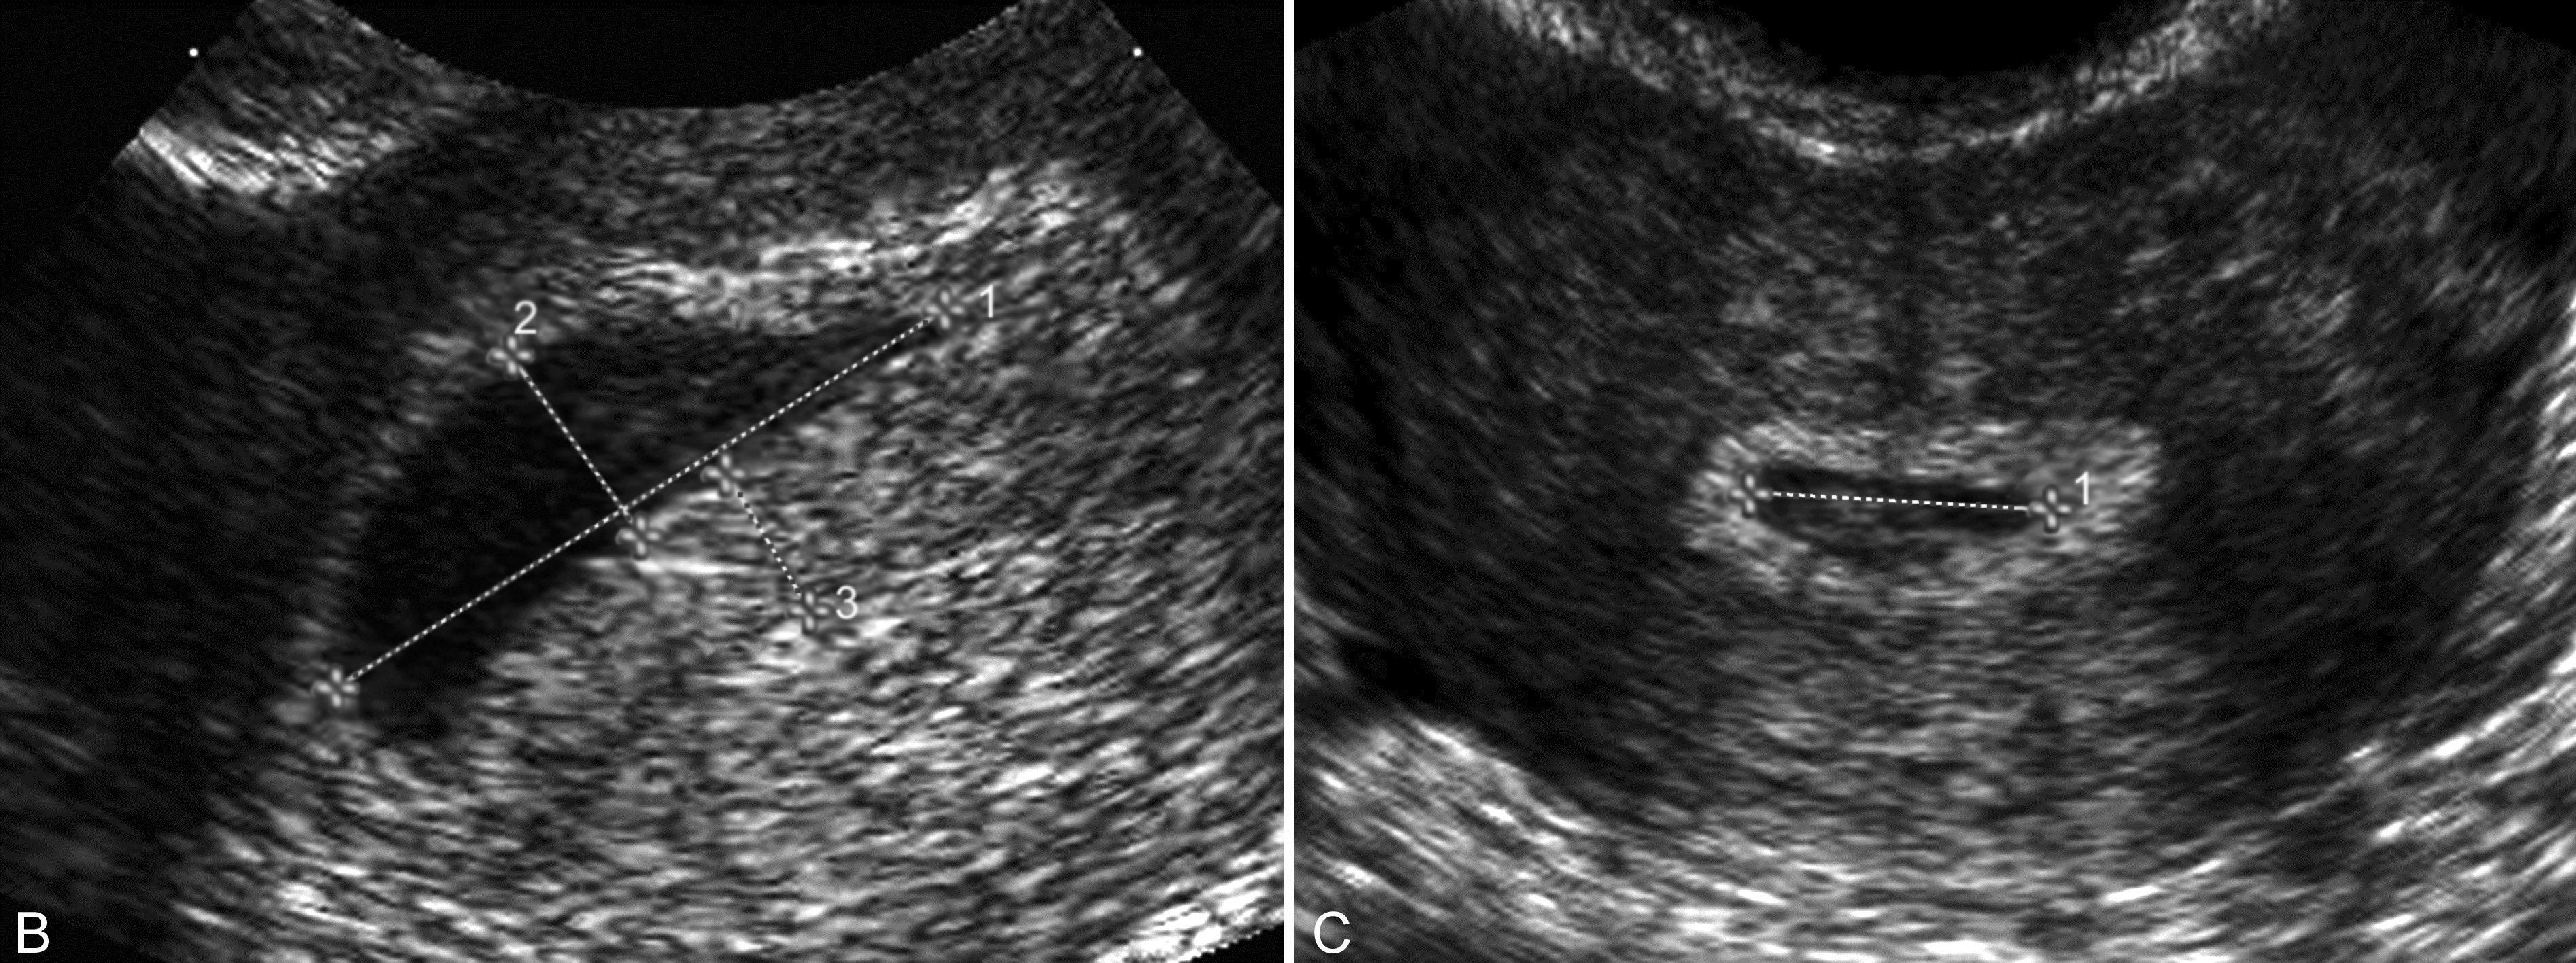

1、子宫增大 在激素的作用下,几乎所有的输卵管妊娠均可引起子宫体积的增大,但大多数小于停经月份;子宫内膜回声增厚,约有10%~20%的患者宫腔内可显示梭形或扁圆形无回声结构(图1,2),称为“假妊娠囊”(false gestational sac)或称为宫腔内积液(intrauterine fluid with ectopic pregnancy)。一般认为,正常的宫内孕囊多位于子宫腔内的一侧,与子宫腔一起形成“双环征”。仔细检查其内部有无卵黄囊及胚胎回声对鉴别宫腔内妊娠和宫腔外妊娠很有价值。部分病人子宫可无明显增大。由于近年来子宫内外同时妊娠的发生率明显增加,当在子宫腔内确定妊娠后,也要仔细检查子宫旁回声,以排除子宫内外同时妊娠的可能。

图1宫外孕并宫内积液:子宫右侧显示异位妊娠(EP),宫腔内显示积液(箭头)

图2宫外孕并宫内积液:B:TVU宫腔内示梭形无回声;C:TVU示宫腔内椭圆形无回声